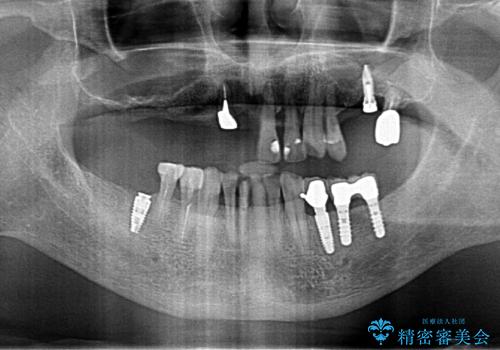

奥歯のインプラント 70代男性

- 奥歯の違和感を主訴に来院された患者様です。

精査したところ、右下の奥歯は大きなう蝕により保存不可能な状態でした。

患者様のご希望により、抜歯後インプラント治療を行いました。